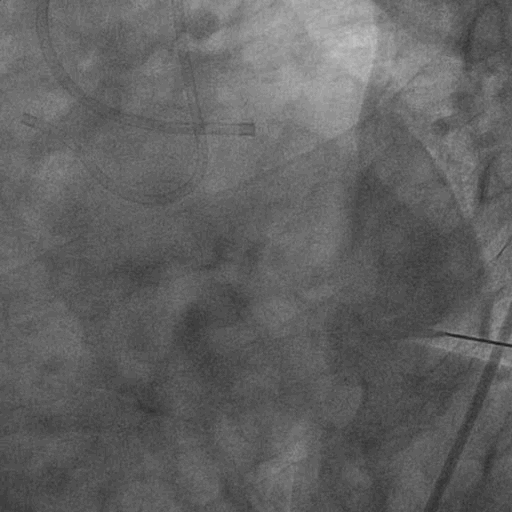

左冠造影:

右冠造影: